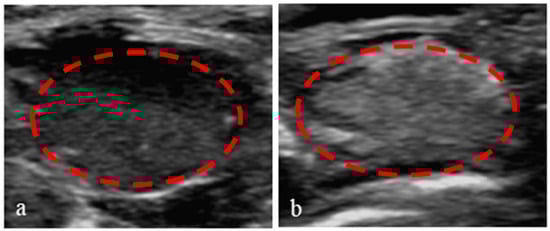

3.8. Application of Nanoparticles in Ultrasound-Enhanced Imaging of Tumors